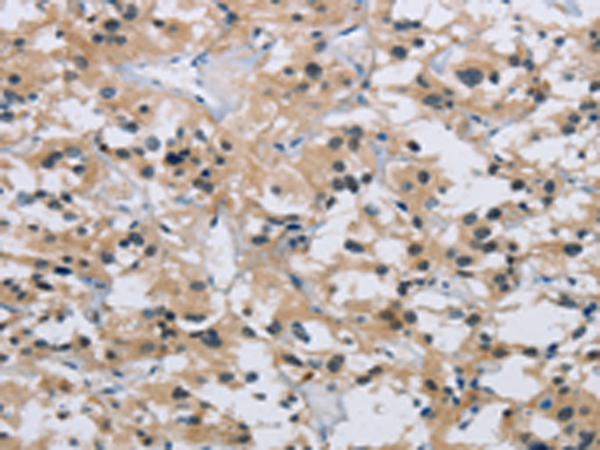

分类: 科研抗体货号: P11830别名: DP5; HARAKIRI应用: IHC反应种属: Human